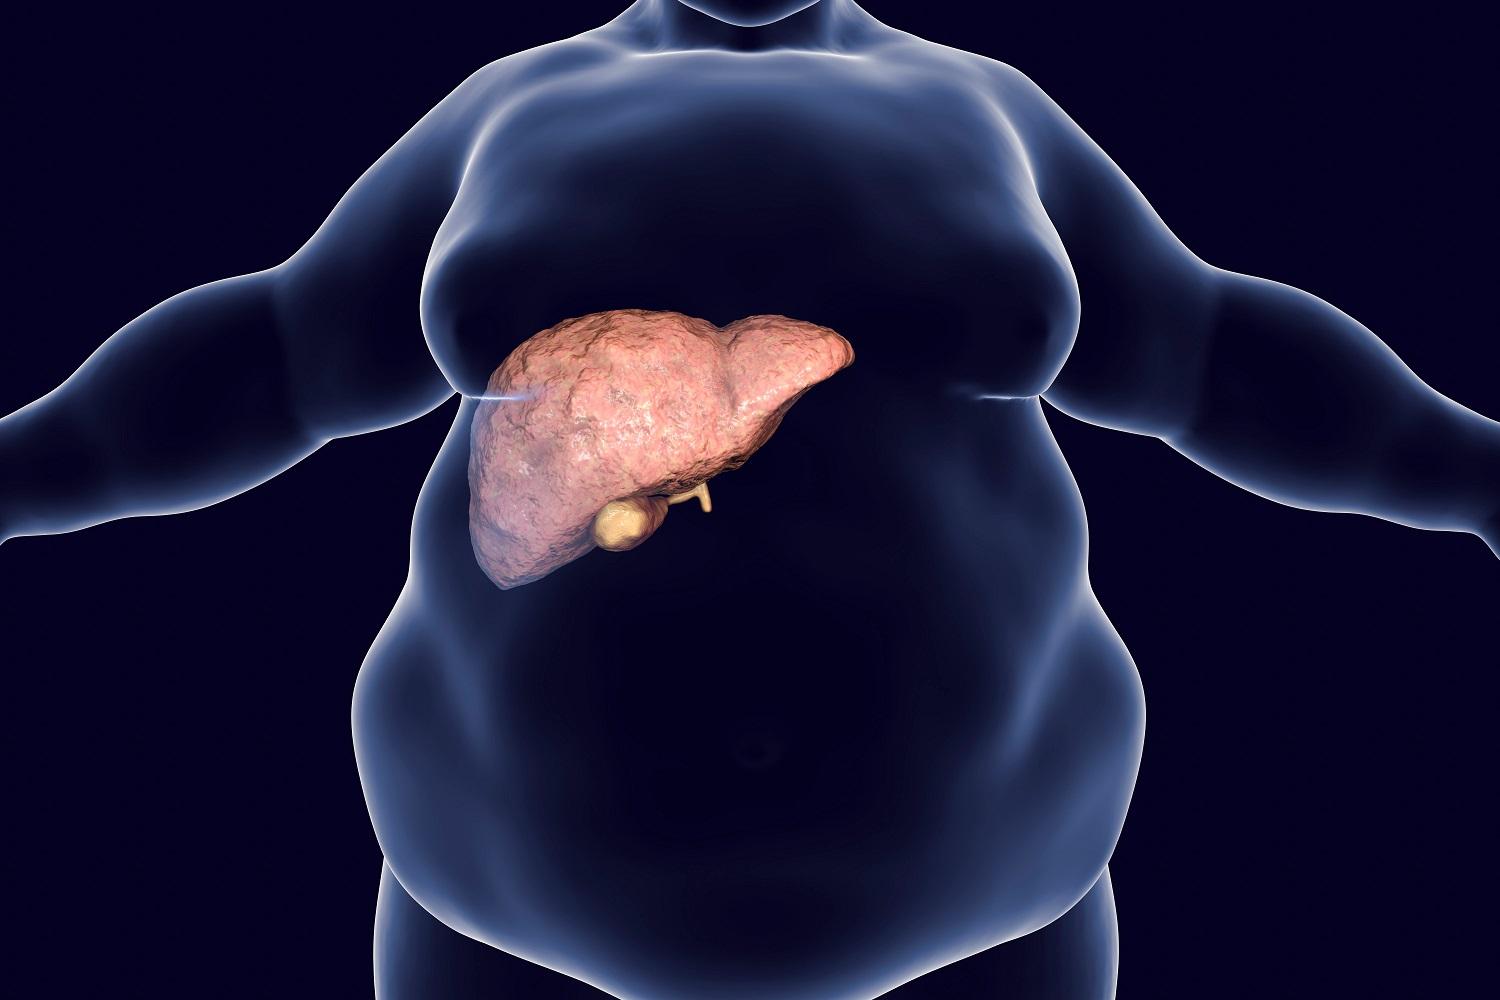

吃得多又郁得少,令脂肪肝愈來愈普通,減肥已經不容易,怎樣才能幫肝臟消脂?最新研究便發現,咖啡、纖維,以及以蔬果、全穀類為主食,配搭適量魚類和禽肉,並常用橄欖油和蒜頭烹調的地中海飲食,都有助改善肝臟健康。

該項在《Nutrients》公布的綜合分析顯示,多種飲食都有助改善非酒精性脂肪肝,當中尤其是咖啡、高纖及地中海飲食可以帶來最大效益。研究更建議攝取纖維對控制脂肪肝有很大幫助,不僅因為纖維有助減少肥胖及維持體重,而且更有助促進腸道健康,對脂肪肝亦有正面影響。

營養攝取是預防脂肪肝的關鍵,一個涵蓋新鮮及原型食物,包括蔬菜、生果及全穀類的飲食,可以促進肝臟健康。

研究人員指出,營養攝取是預防脂肪肝的關鍵,一個涵蓋新鮮及原型食物,包括蔬菜、生果及全穀類的飲食,可以促進肝臟健康。而地中海飲食就含有豐富的單元和多元飽和脂肪酸、抗氧化劑、纖維及植物蛋白,可以阻截脂肪肝惡化。

非酒精性脂肪肝可引致慢性肝病,甚至導致細胞病變,目前並無針對性的治療可以對付脂肪肝。

非酒精性脂肪肝可引致慢性肝病,甚至導致細胞病變,目前並無針對性的治療可以對付脂肪肝。雖然遺傳和環境因素與脂肪肝形成有關,但不同的研究均顯示,實踐健康飲食可以減少肝臟脂肪及炎症,故此調整飲食及生活模式是治療脂肪肝的主要措施。